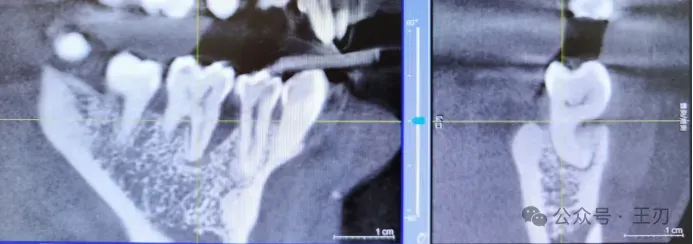

因为患者三个月前的全景片和咬合翼片都没能看出明显的骨吸收,根据探诊的结果我给她拍了CBCT:

因为CBCT是三维影像,把视图拉到靠舌侧(上图),可以发现46近中很深的牙槽骨吸收,已经到达根尖。而把视图拉到靠颊侧(下图),在同样位点46的近中就看不到明显骨吸收。这就是为什么我们不能单单凭借X光片去判断患者是否有牙周炎,探诊是最简便,无害,客观的检查手段。